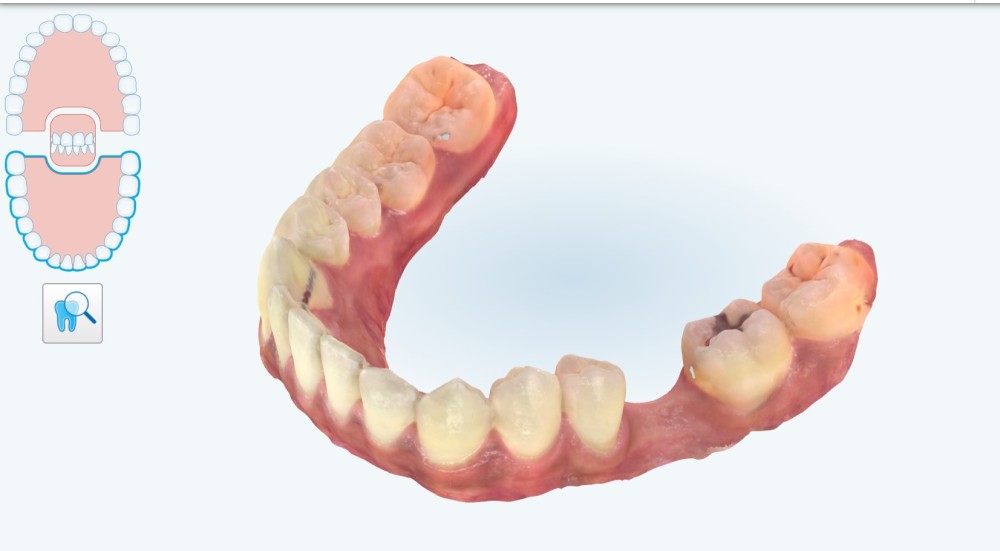

Pour cela nous décidons de poser notre implant de façon « Full guidé », c’est-à-dire planifié en amont dans une position alliant un placement optimal osseux et prothétique. Nous aurons besoin d’une empreinte numérique qui va nous fournir un fichier STL (fig. 1) , ainsi que les information sur l’os fournies par le cone-beam (CBCT) . Nous décidons à ce stade de faire modéliser le guide par une plateforme de conception (design4me) qui s’occupera du matching de nos DATA. Après validation de la planification nous recevons notre fichier (fig. 2) prêt à être imprimé localement grâce à une imprimante 3D (Nextdent).

3 mois après cicatrisation , nous reprenons notre camera en main, et cette fois ci, nous allons prendre l’empreinte de notre « scanbody » qui est le transfert d’empreinte numérique (fig. 4) correspondant à notre implant (Megagen). C’est la que la magie opère… Fini les portes empreintes individuels, à perforer etc. On place le scanbody et on prends l’empreinte (haut , bas , occlusion). On peut même prendre le profil d’émergence sur un scan supplémentaire en quelques secondes.